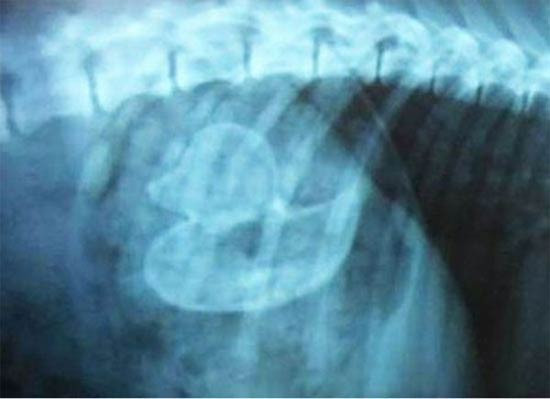

Köpeğin midesinden çıkana bak!